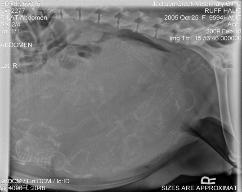

Weekly Report *Just Born* 2-18-09 6 Females 4 Males Wish us good health over the next few days ^^^^^^^^ 5 Days old 9 DAYS Old 1 Week old 2 weeks old Our eyes are just starting to open and we are walking pretty good for not being able to see yet. 3 weeks This is the 2 girls that live with Hopper's baby 3 weeks 3 1/2 Weeks 4 weeks We have our collars on now 5 weeks 6 weeks old CLICK HERE FOR INDIVIDUAL SHOTS OF EACH PUP 7 WEEKS 8 WEEKS |